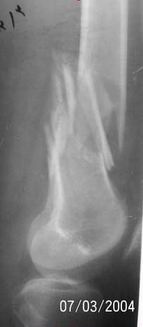

A 34 year old male was injured in a car accident.

The femur injury was treated by long retrograde interlocking nail.

It seems you`d better to remove the nail and fix the

bone fragmenrs with DCS plate.

I would expect healing though alignment could have been better if Poller screw or temporary wire was used.